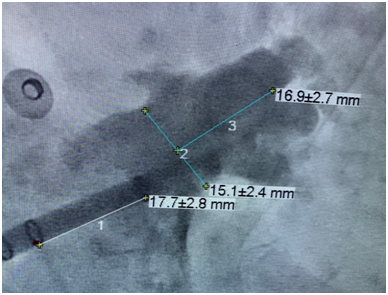

術前心臟超聲左心耳示意圖

術中左心耳造影